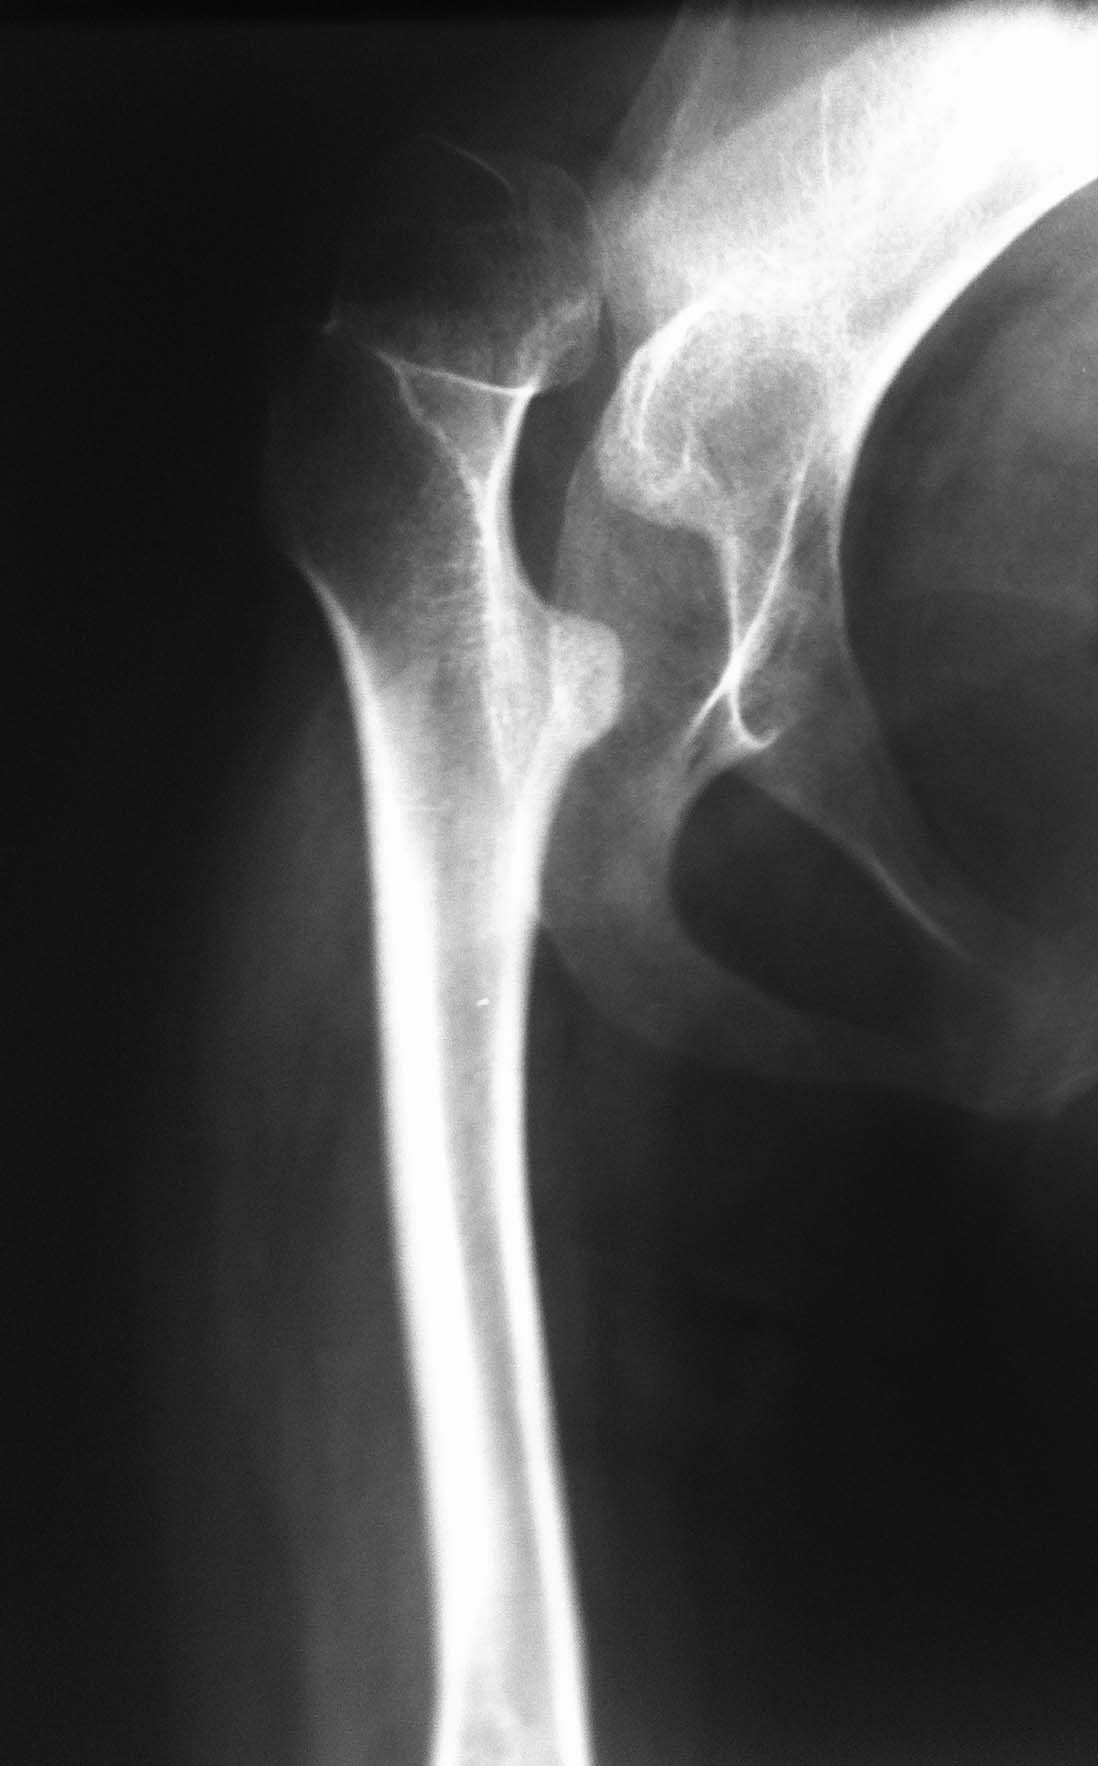

ДЦП, Сколиоз и вывих бедра.

Пациентка 1992 г.р. Болеет ДЦП с рождения. до 2005 г. наблюдалась у неврологов , ходила с поддержкой. В 2005 г. перелом средней трети бедра. Лечилась консервативно в больнице Краснодара.

После лечения постепенно стало наростать укорочение конечности и искривление позвоночника.На представленных Р-гр состояние на сегодняшний день.больная занимает вынужденное полулежачее состояние.Вопрос - где нибудь на просторах РФ могут помочь?????